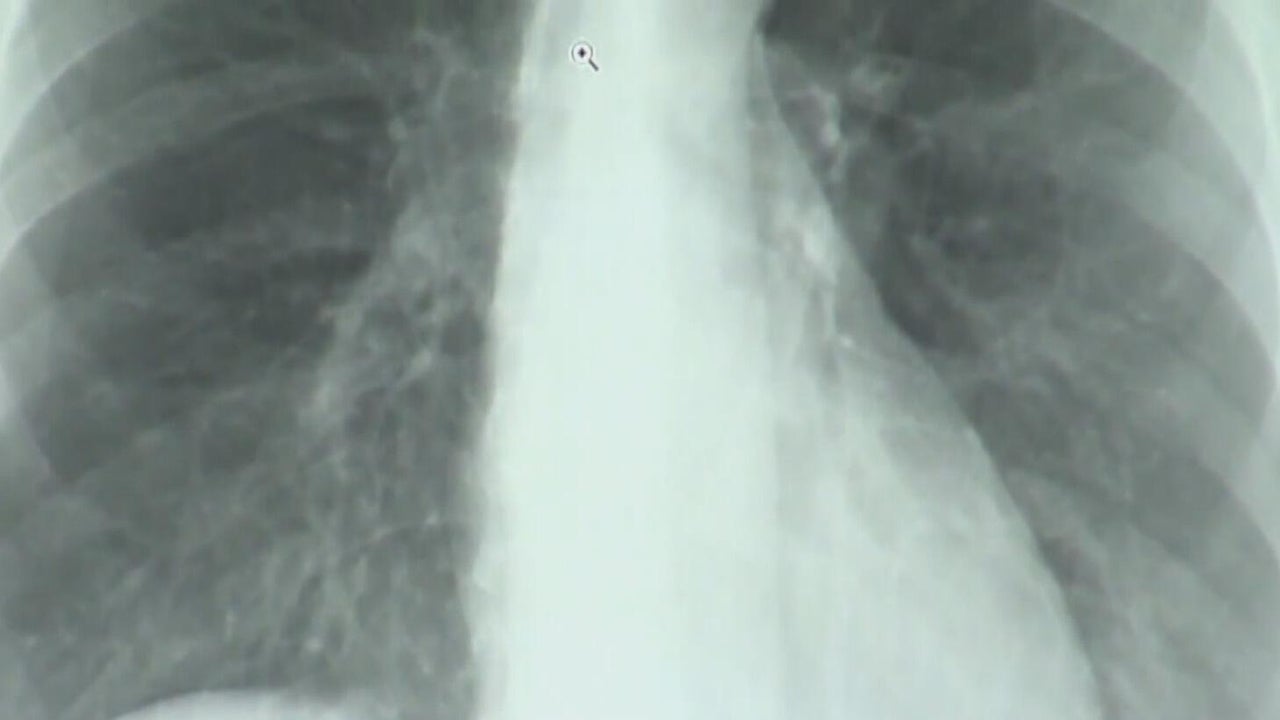

Report shows improvements in lung cancer treatment in Pennsylvania

Lung cancer is the leading cause of cancer-related deaths in the U.S.